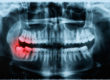

Periodontal disease affects the structures in the mouth that support the teeth – gums and bone. This is a chronic (persists over time) disease that often has no symptoms, especially in its early stages. Don’t be fooled. Unless it is properly treated, the disease will worsen and the damage leads to tooth loss.

The disease starts when tartar and bacteria under the gum line lead to infection and as the body fights the infection, the gums become inflamed (irritated and swollen). Deep pockets form between tooth and gum, making plaque harder to remove. As the disease advances, bone damage occurs and can lead to tooth loss.